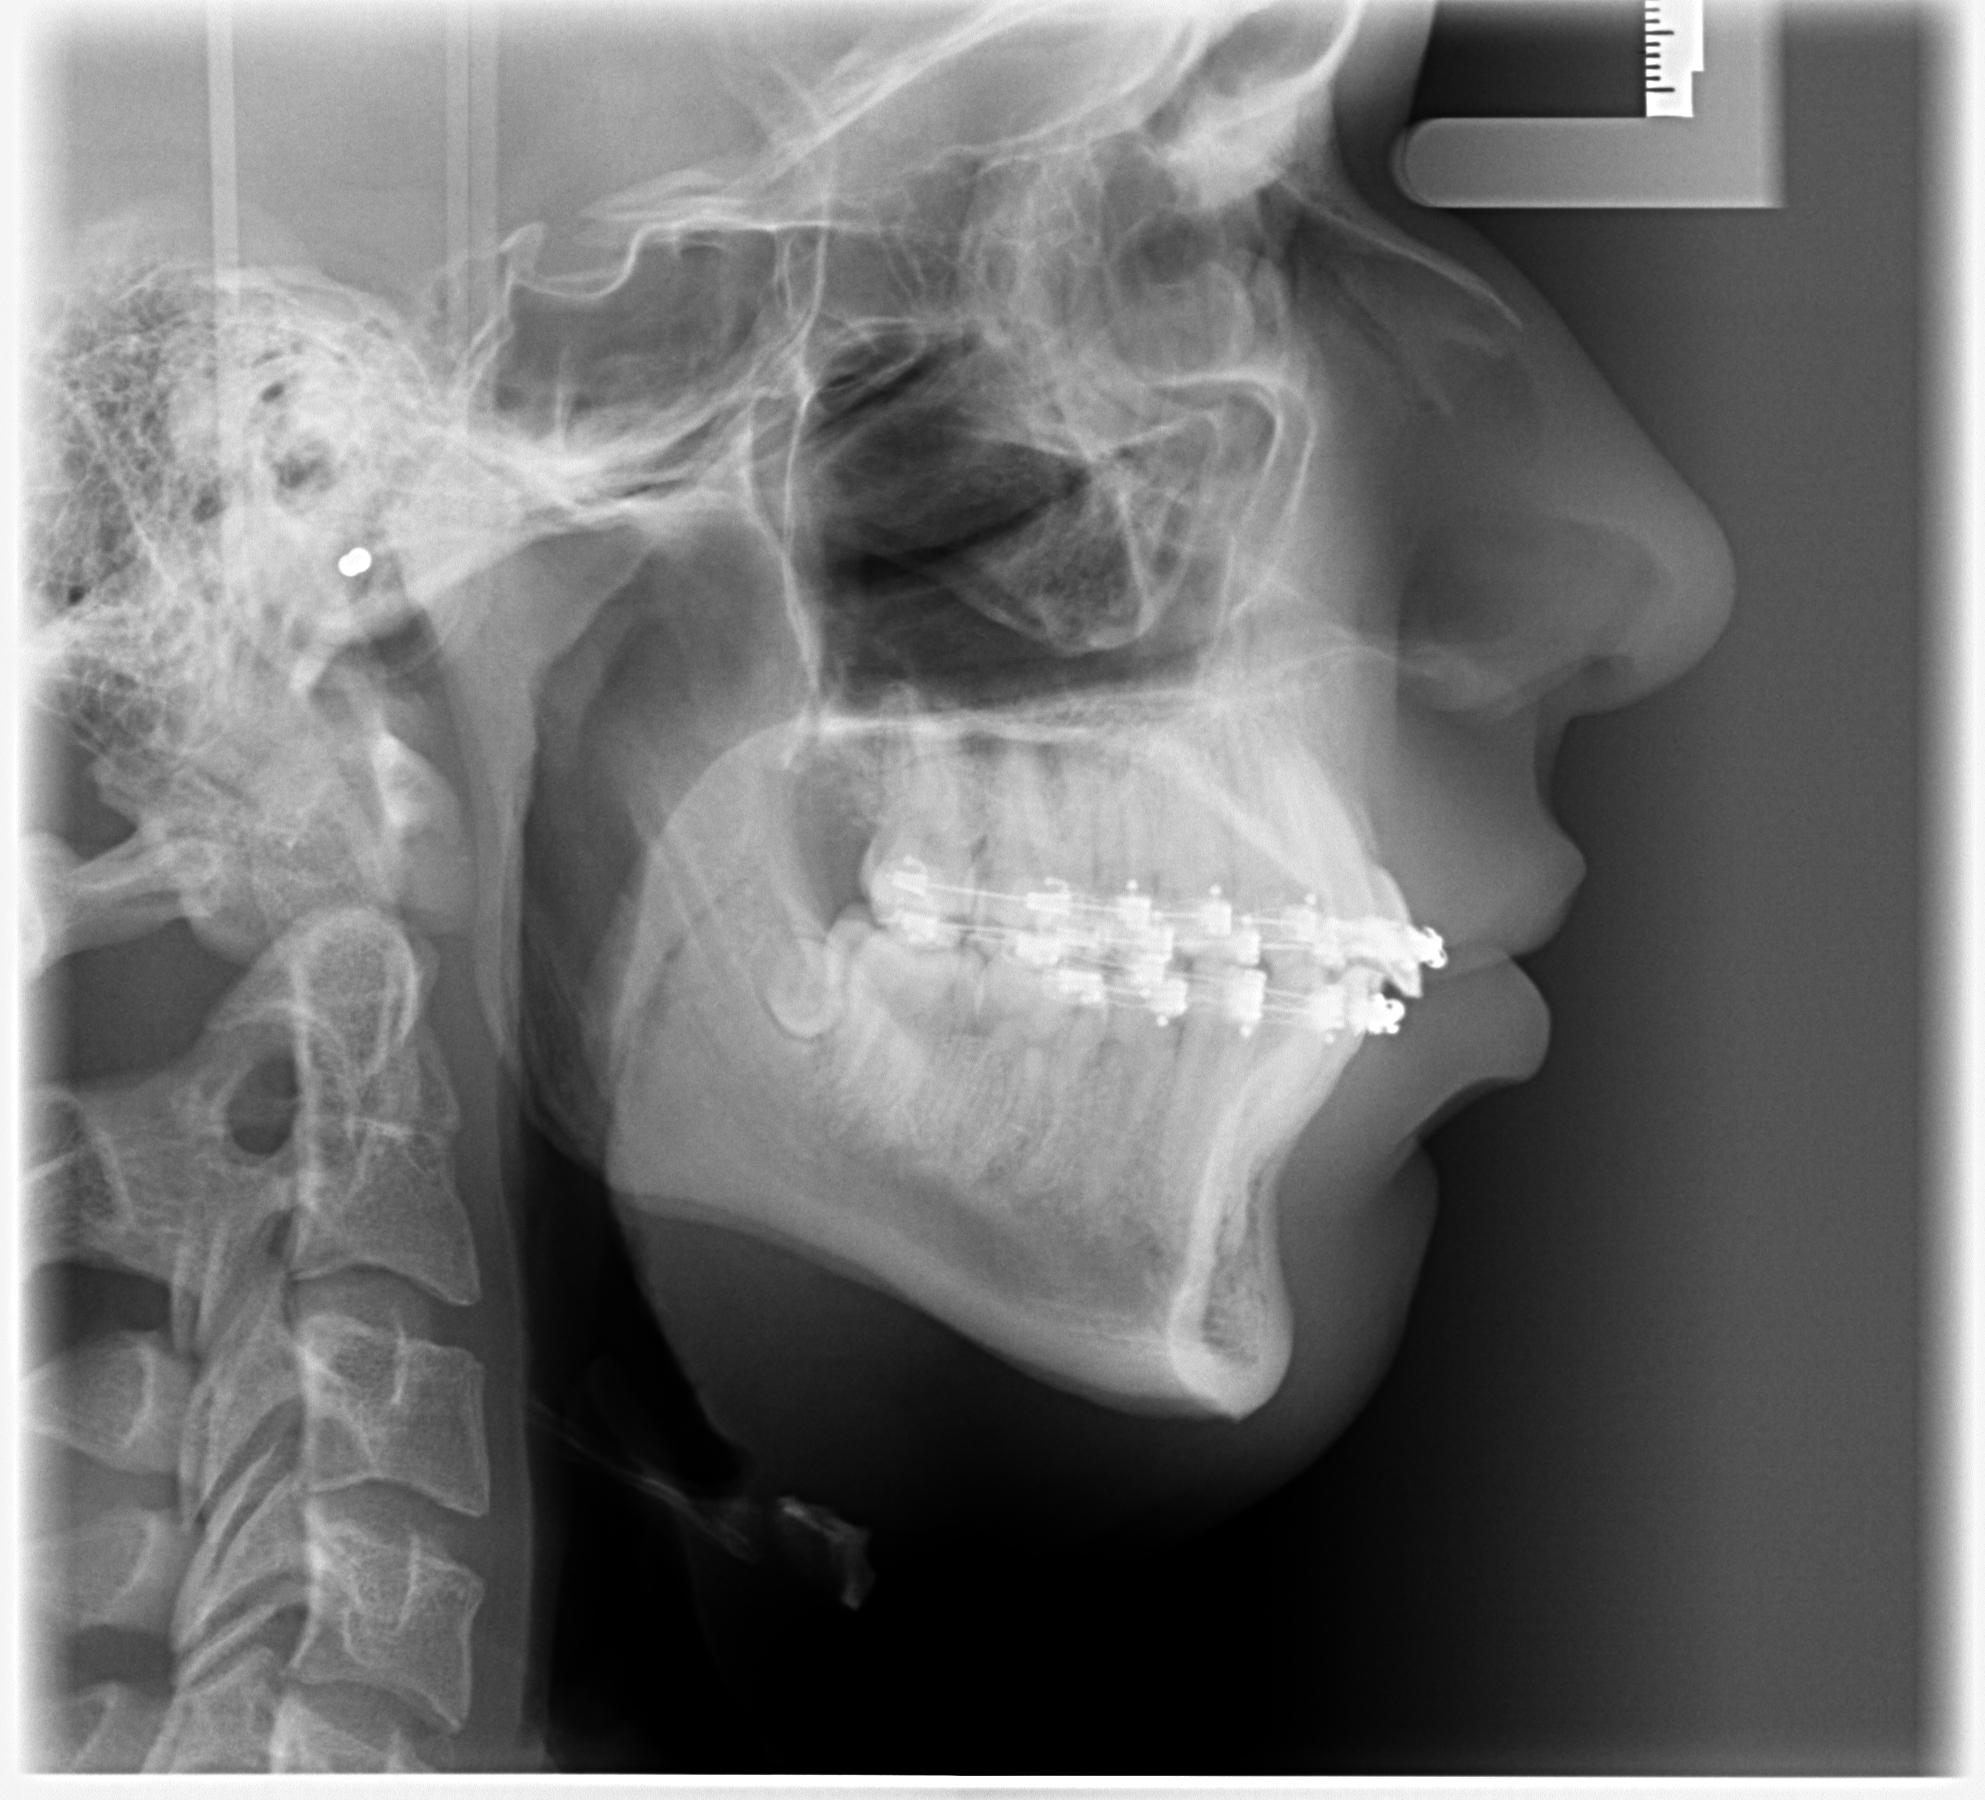

After

1770743494219

1770743506277

I'm still very bloated, what do you think abt the ascension tho? How big will it be?